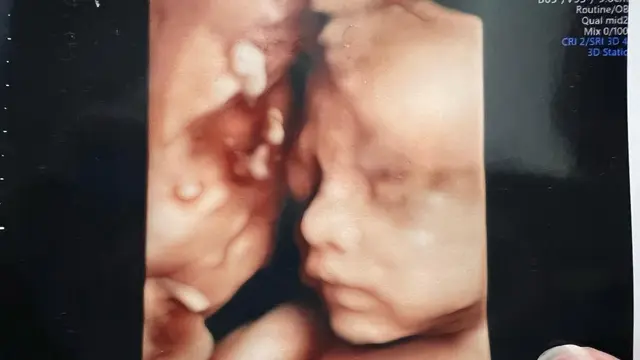

Hasil USG itu pun diunggah Nella di akun Instagram pribadinya. Foto USG model 3D tersebut memperlihatkan wajah anak kedua Nella. Hidung dari calon anak kedua Nella tampak mancung seperti ibudanya.

Nella Kharisma pun bertanya-tanya kepada para followers-nya soal wajah calon anak keduanya. "Kira-kira mirip siapa ya? Papah @doryharsa , mamah @nellakharisma atau mbak @gendhismadaharsa ππ," tulis Nella sebagai keterangan foto.

Postingan Nella ini pun langsung mendapatkan berbagai macam komentar dari netizen. Sebagian besar dari netizen menduga jika calon anak kedua Nella dan Dory berjenis kelamin laki-laki. Beberapa netizen juga menganggap jika wajah calon anak kedua Nella mirip dengan wajah sang ayah.

"Yg hamil mamaknya,yg ngrasain sakit pas nglahirin mamaknya,,,giliran keluar mukanya mirip sama bapaknyaπππ," ujar seorang netizen. "Ini kayanya lebih ke papanya deh π.. Klo mba gendhis perpaduan antara papa mamanya π," timpal netizen lainnya. "Cowok kayaknya ya.. mirip mas dorπ," sahut netizen lainnya.